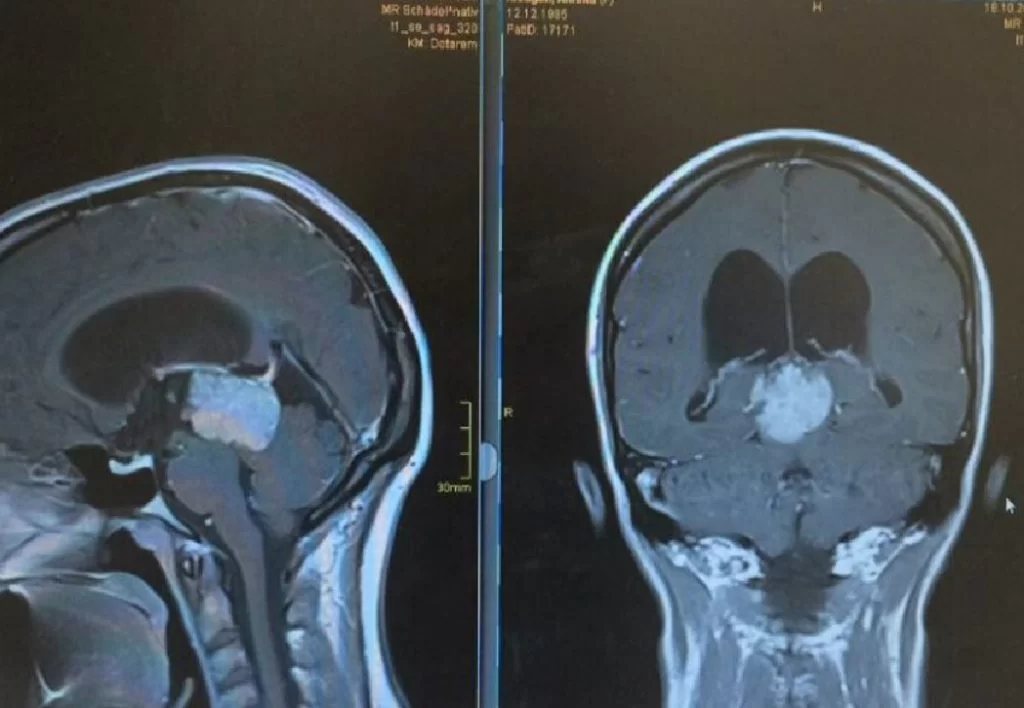

Μηνιγγίωμα περιοχής Επίφυσης

Ασθενής γυναίκα, 52 ετών η οποία παρουσίασε υπακουσία και επεισόδια πάρεσης του προσώπου. Ο απεικονιστικός έλεγχος με μαγνητική τομογραφία ανέδειξε ευμεγέθη όγκο στην περιοχή της